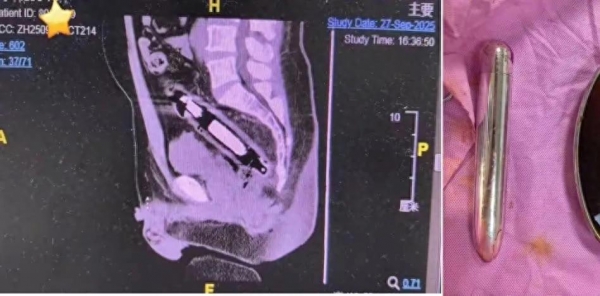

副主任医师李心茹一看这情况,心里咯噔一下。这可不是开玩笑的,三十厘米的金属异物在直肠里乱晃,简直就是肠道里的"定海神针",不,是"穿肠利剑"!这东西要是再往深处走,或者姿势不对,随时可能把肠壁划破,那可就是腹膜炎,要人命的大事!李医生当机立断,别等了,手术室见!麻醉、消毒、开台,一气呵成。最终,在医生们巧夺天工的操作下,这根惹祸的金属棍被成功"请"了出来,王先生也算是捡回了一条命。